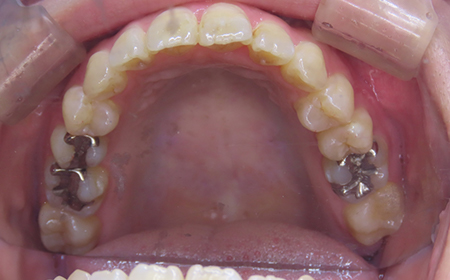

CASE09

Before

After

| 施術名 |

インビザラインコンプリヘンシブを用いた矯正治療(叢生) |

| 治療期間 |

1.5年 |

| 治療費 |

880,000円(税込) |

| リスク |

マウスピース装置により疼痛・咬合時痛を生じる事があります。割れたり壊れたりする事があります。 |